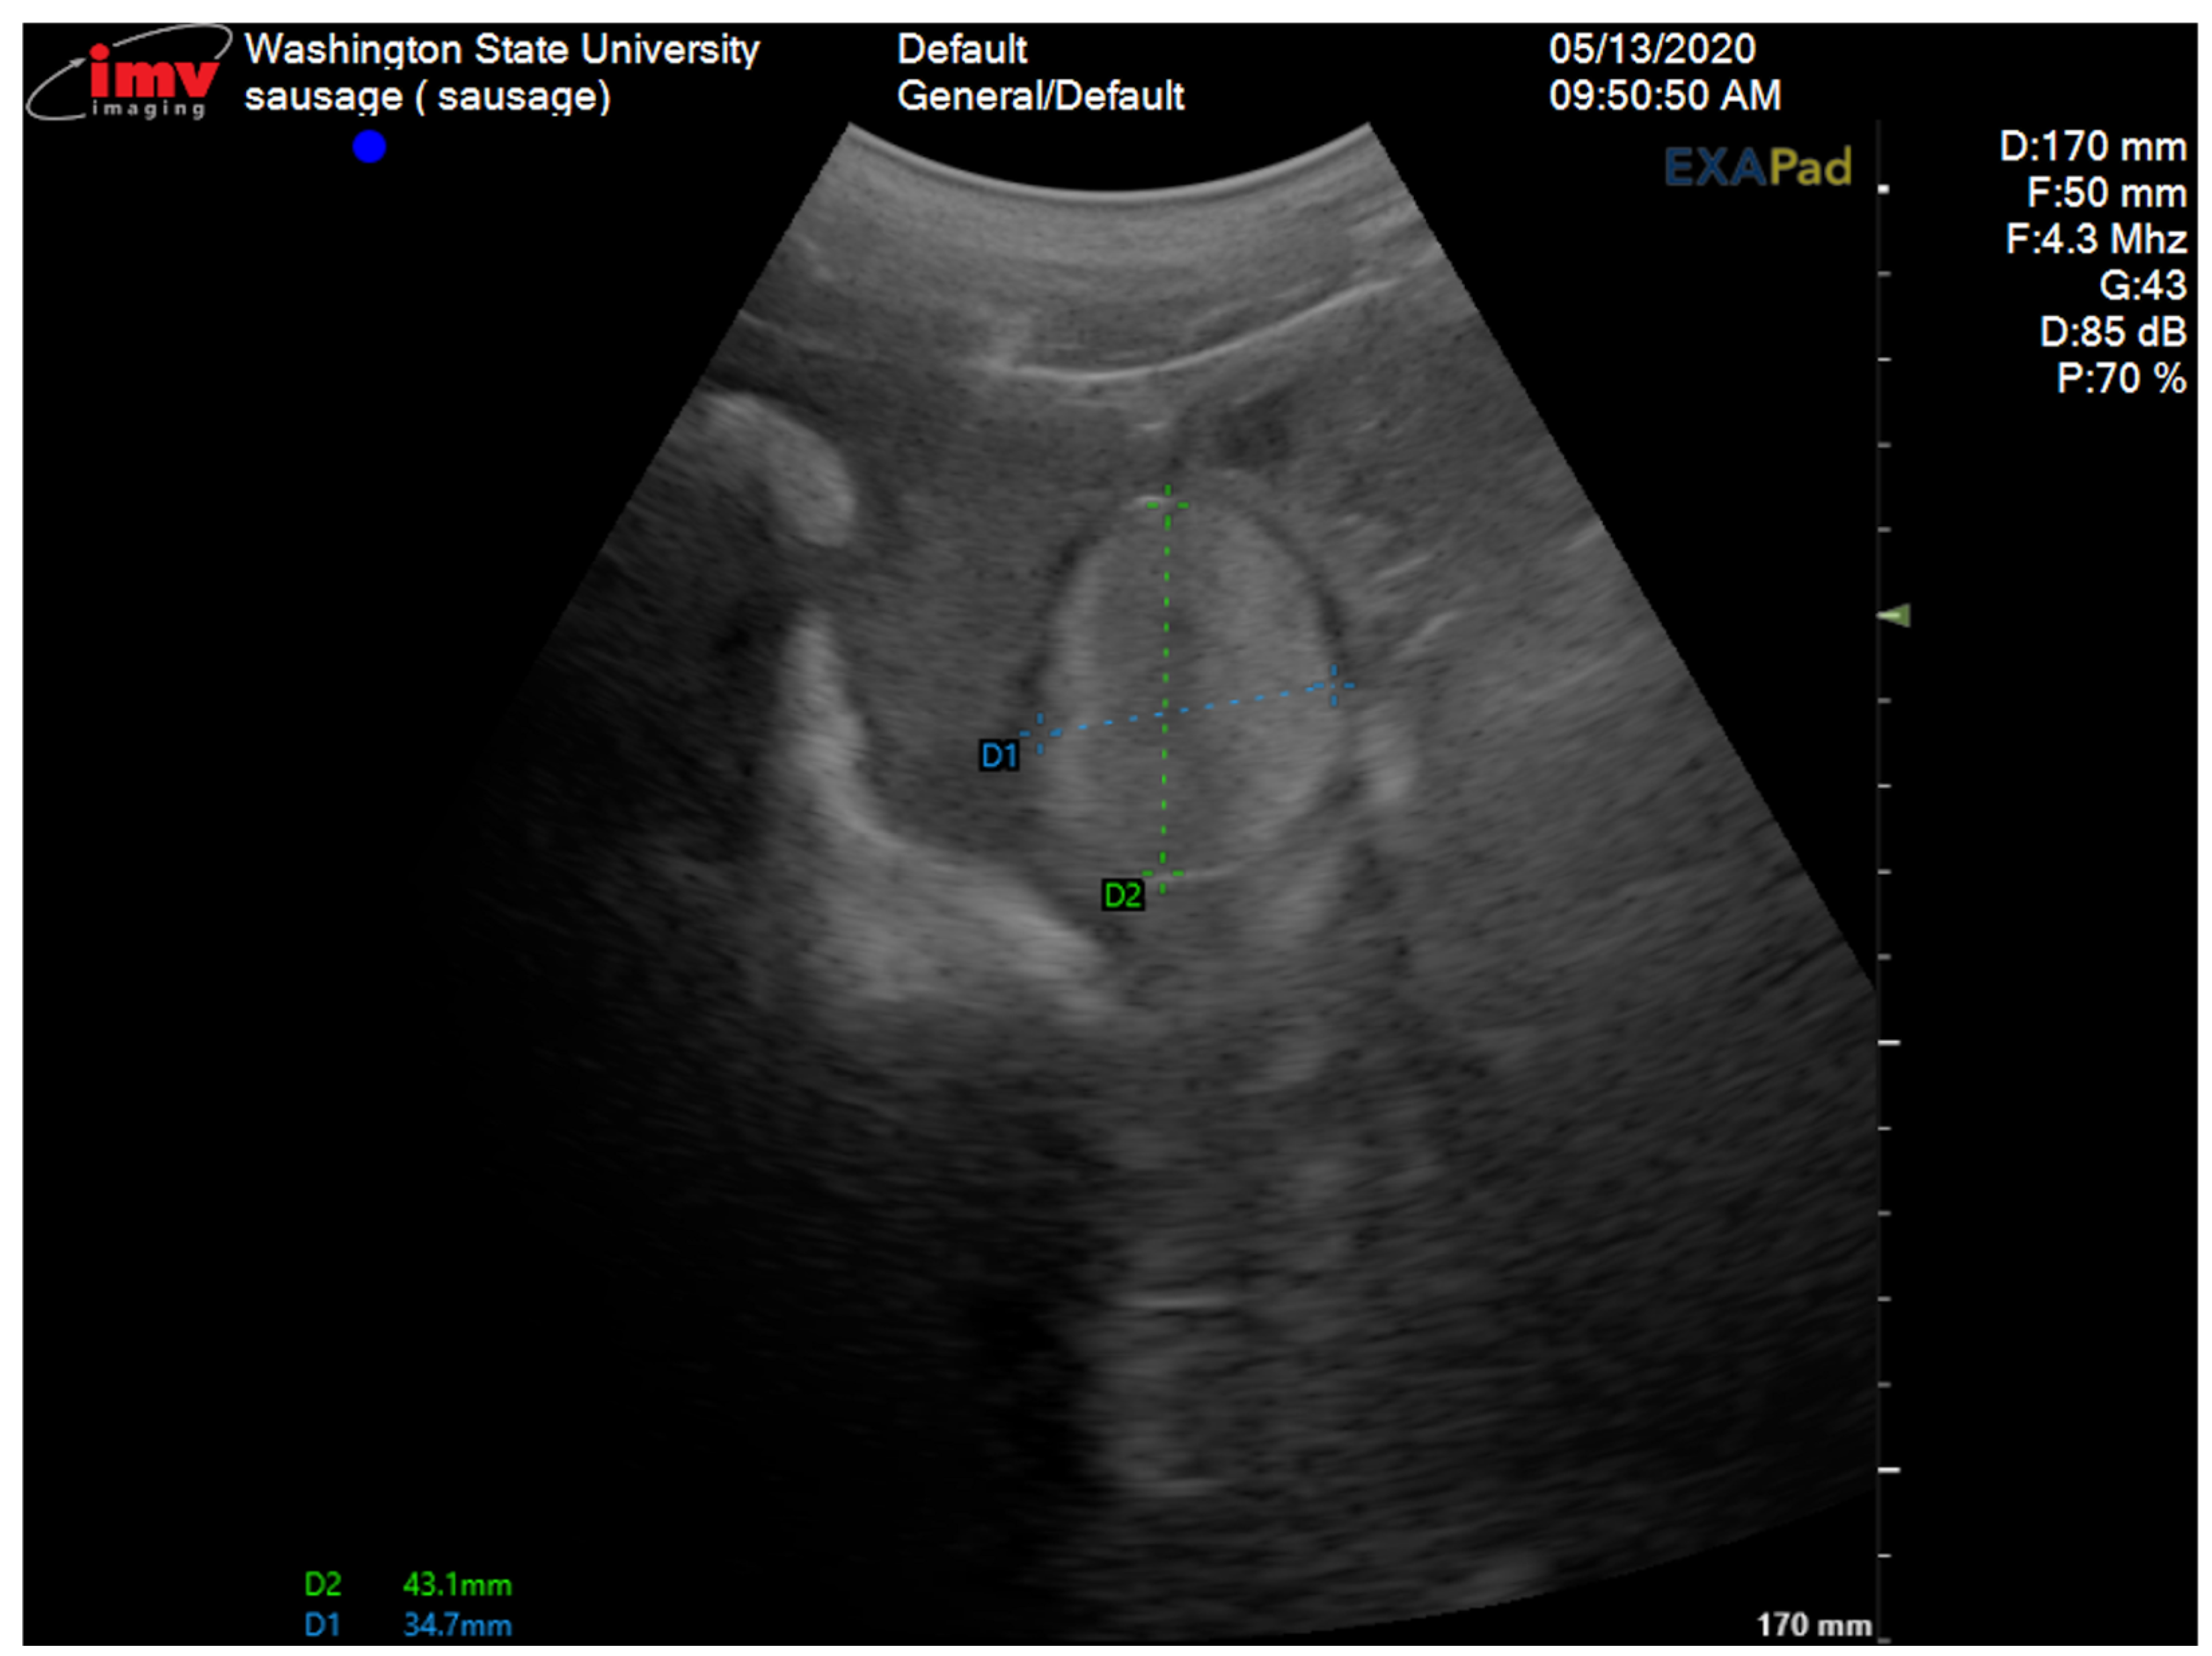

2.1. Surgical Procedure

2.2. Histopathology

2.3. Clinical Outcome